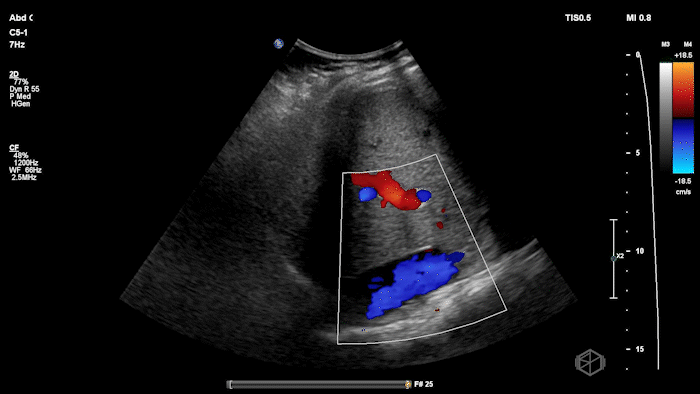

She grabbed the probe, and working with Dr. Zimmerman, saw the following:

There is moderate free fluid, no obvious pleural effusions. The bilateral ovaries are enlarged with multiple cystic structures. There are normal arterial and venous waveforms for both ovaries.

• Typical ultrasound findings: enlarged ovaries with multiple cysts/follicles; free fluid (ascites) and in more severe cases pleural or pericardial effusions. (📚 PMID: 27998636)

• Preserved ovarian arterial and venous flow helps distinguish OHSS from acute ovarian torsion, where flow may be compromised.